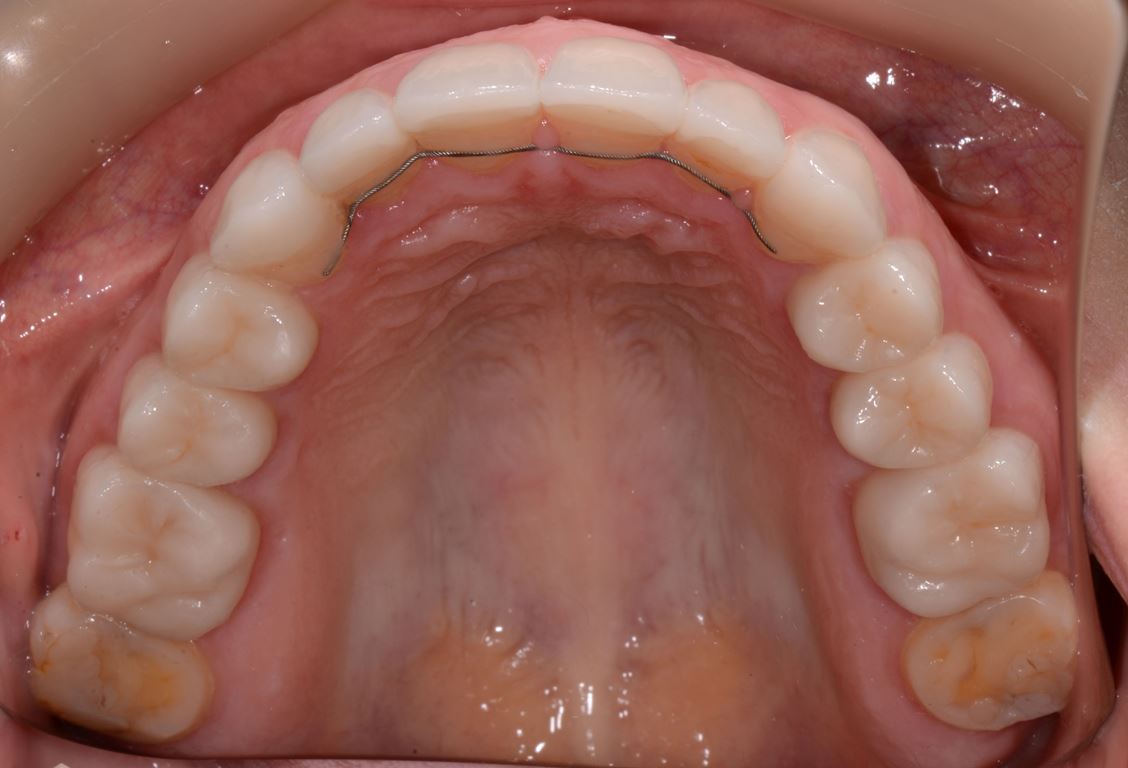

W pierwszym etapie diagnostycznym wykonano zdjęcia zewnątrz- i wewnątrzustne (ryc. 1-12).

Bezpośrednio po usunięciu zębów rozpoczęto leczenie ortodontyczne, które trwało 15 miesięcy i pozwoliło na uzyskanie zaplanowanych wcześniej pozycji zębów (ryc. 22-24).